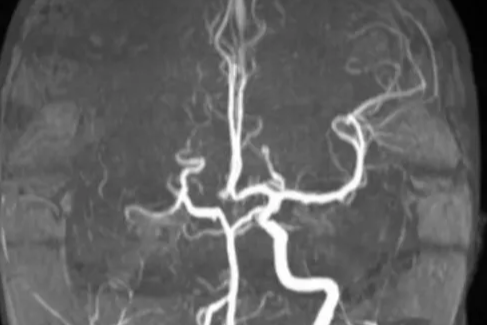

为她,打赢这场头脑保卫战!